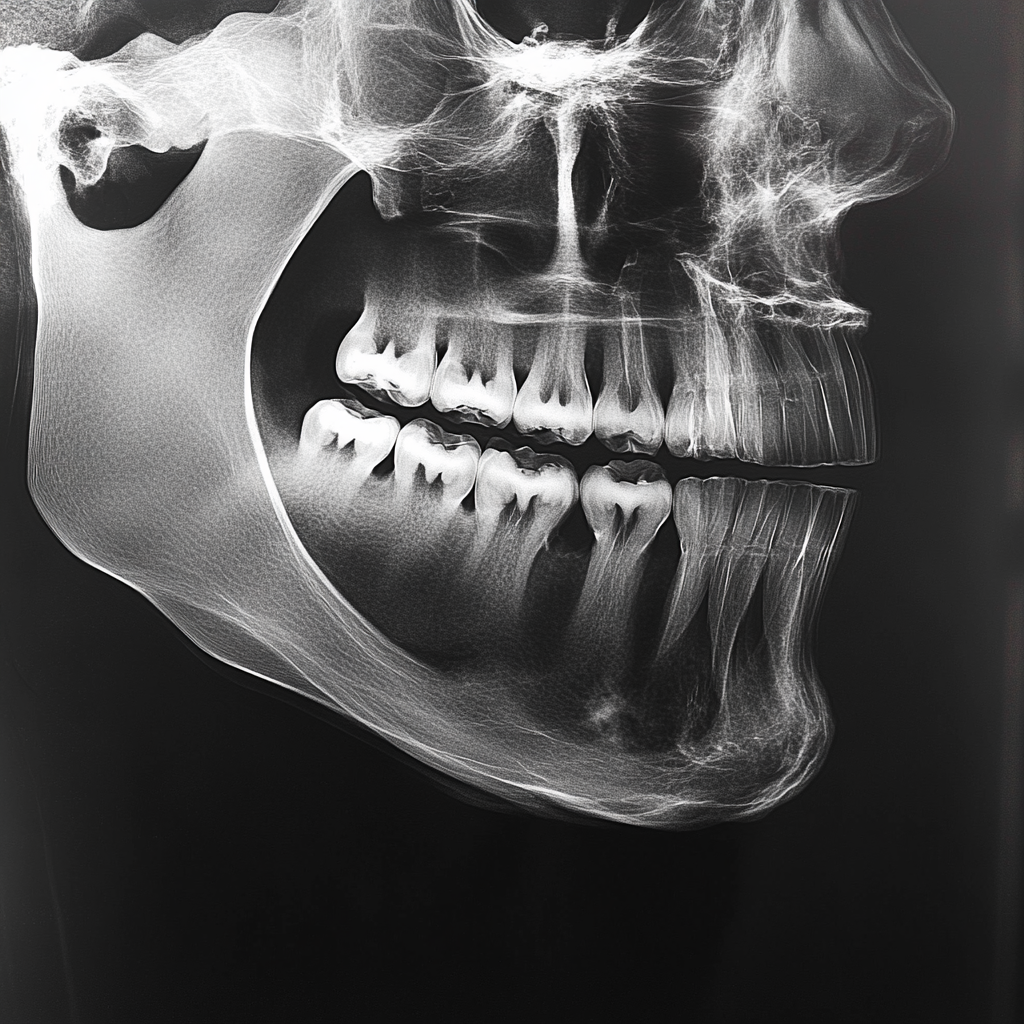

- 사전 진단: 엑스레이로 사랑니의 위치와 상태를 확인합니다.